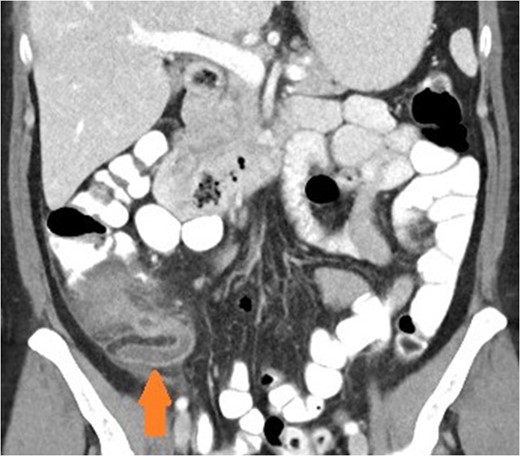

Coronal view of patient with caecal carcinoma. Normal (non-dilated) appendix (arrow).

There are a number of CT features that help distinguish bowel wall thickening from malignant and benign causes [3]. A neoplastic cause is suggested if there is focal bowel wall thickening (less than 5 cm of extension) which is typically asymmetrical and eccentric. These may have homogeneous contrast enhancement due to infiltration of a tumour mass, or a heterogeneous areas of low attenuation from ischaemia and necrosis, findings with a sensitivity of up to 97% [4]. Malignancy may also have shouldered edges as opposed to tapering transition to normal bowel wall. Appendiceal dilatation, if present, may be thin walled and without inflammatory stranding due to a gradual obstructive process, although appendicitis can be a presenting symptom for carcinoma. Regional lymphadenopathy and distal metastases, when present, support the diagnosis.